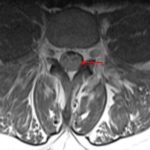

Age: 38

Sex: Male

Indication: Gradual onset bilateral leg weakness over several months

- Thickening and enhancement involving nearly all of the nerve roots of the cauda equina, most pronounced below the level of L3-L4

- Chronic inflammatory demyelinating polyneuropathy (CIDP)

Thickening and enhancement involving nearly all of the nerve roots of the cauda equina, which is most consistent with chronic inflammatory demyelinating polyneuropathy (CIDP) given the reported gradual onset. Recommend correlation with CSF analysis.